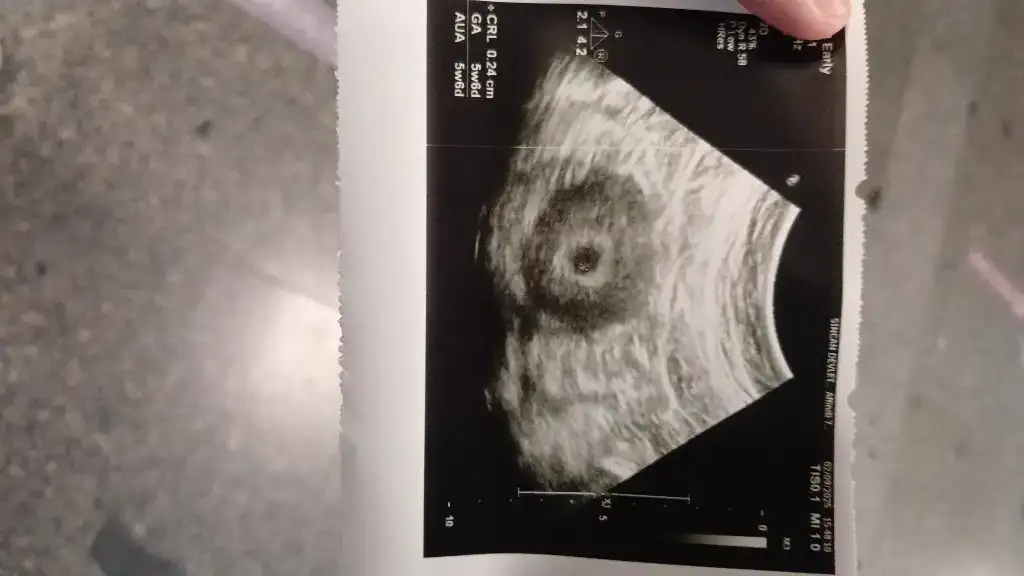

Bence normal görünüyor canım hiç endişe etmeKızlar regle göre 6+3 ama ultrasonda 5+6 çıktı embriyoda 2.5 mm mis anlayan var mı her şey yolunda mı bu doktorlar alelacele muayene ediyor hiç açıklama yapmadan